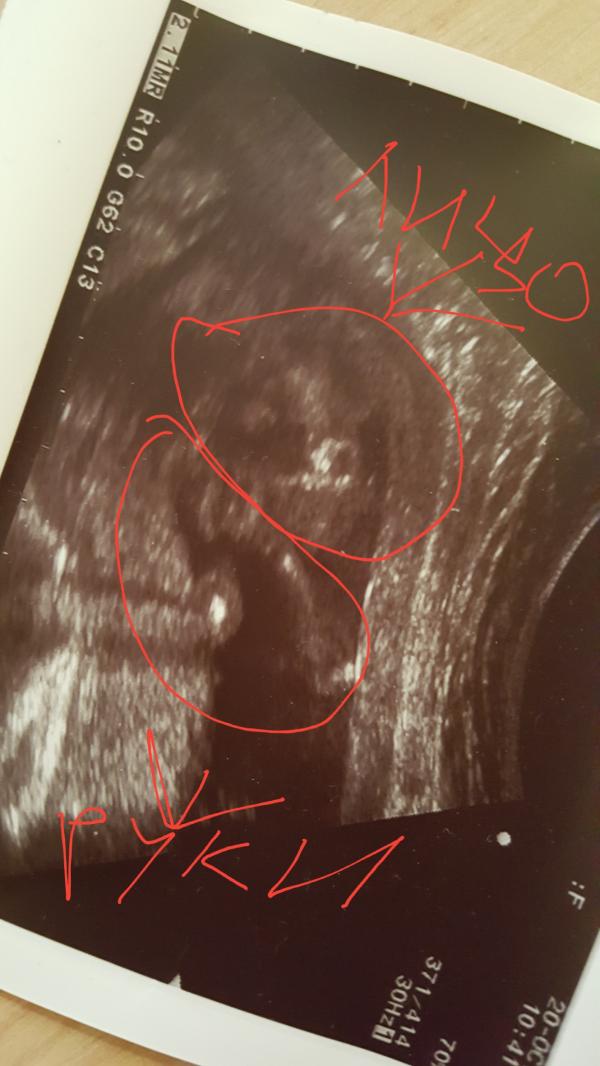

Как я объясняла подруге кто изображен на фото узи 😁

В ответ я получила: какая красотка, на тебя похожа 😆 кстати, у нас девочка 💙